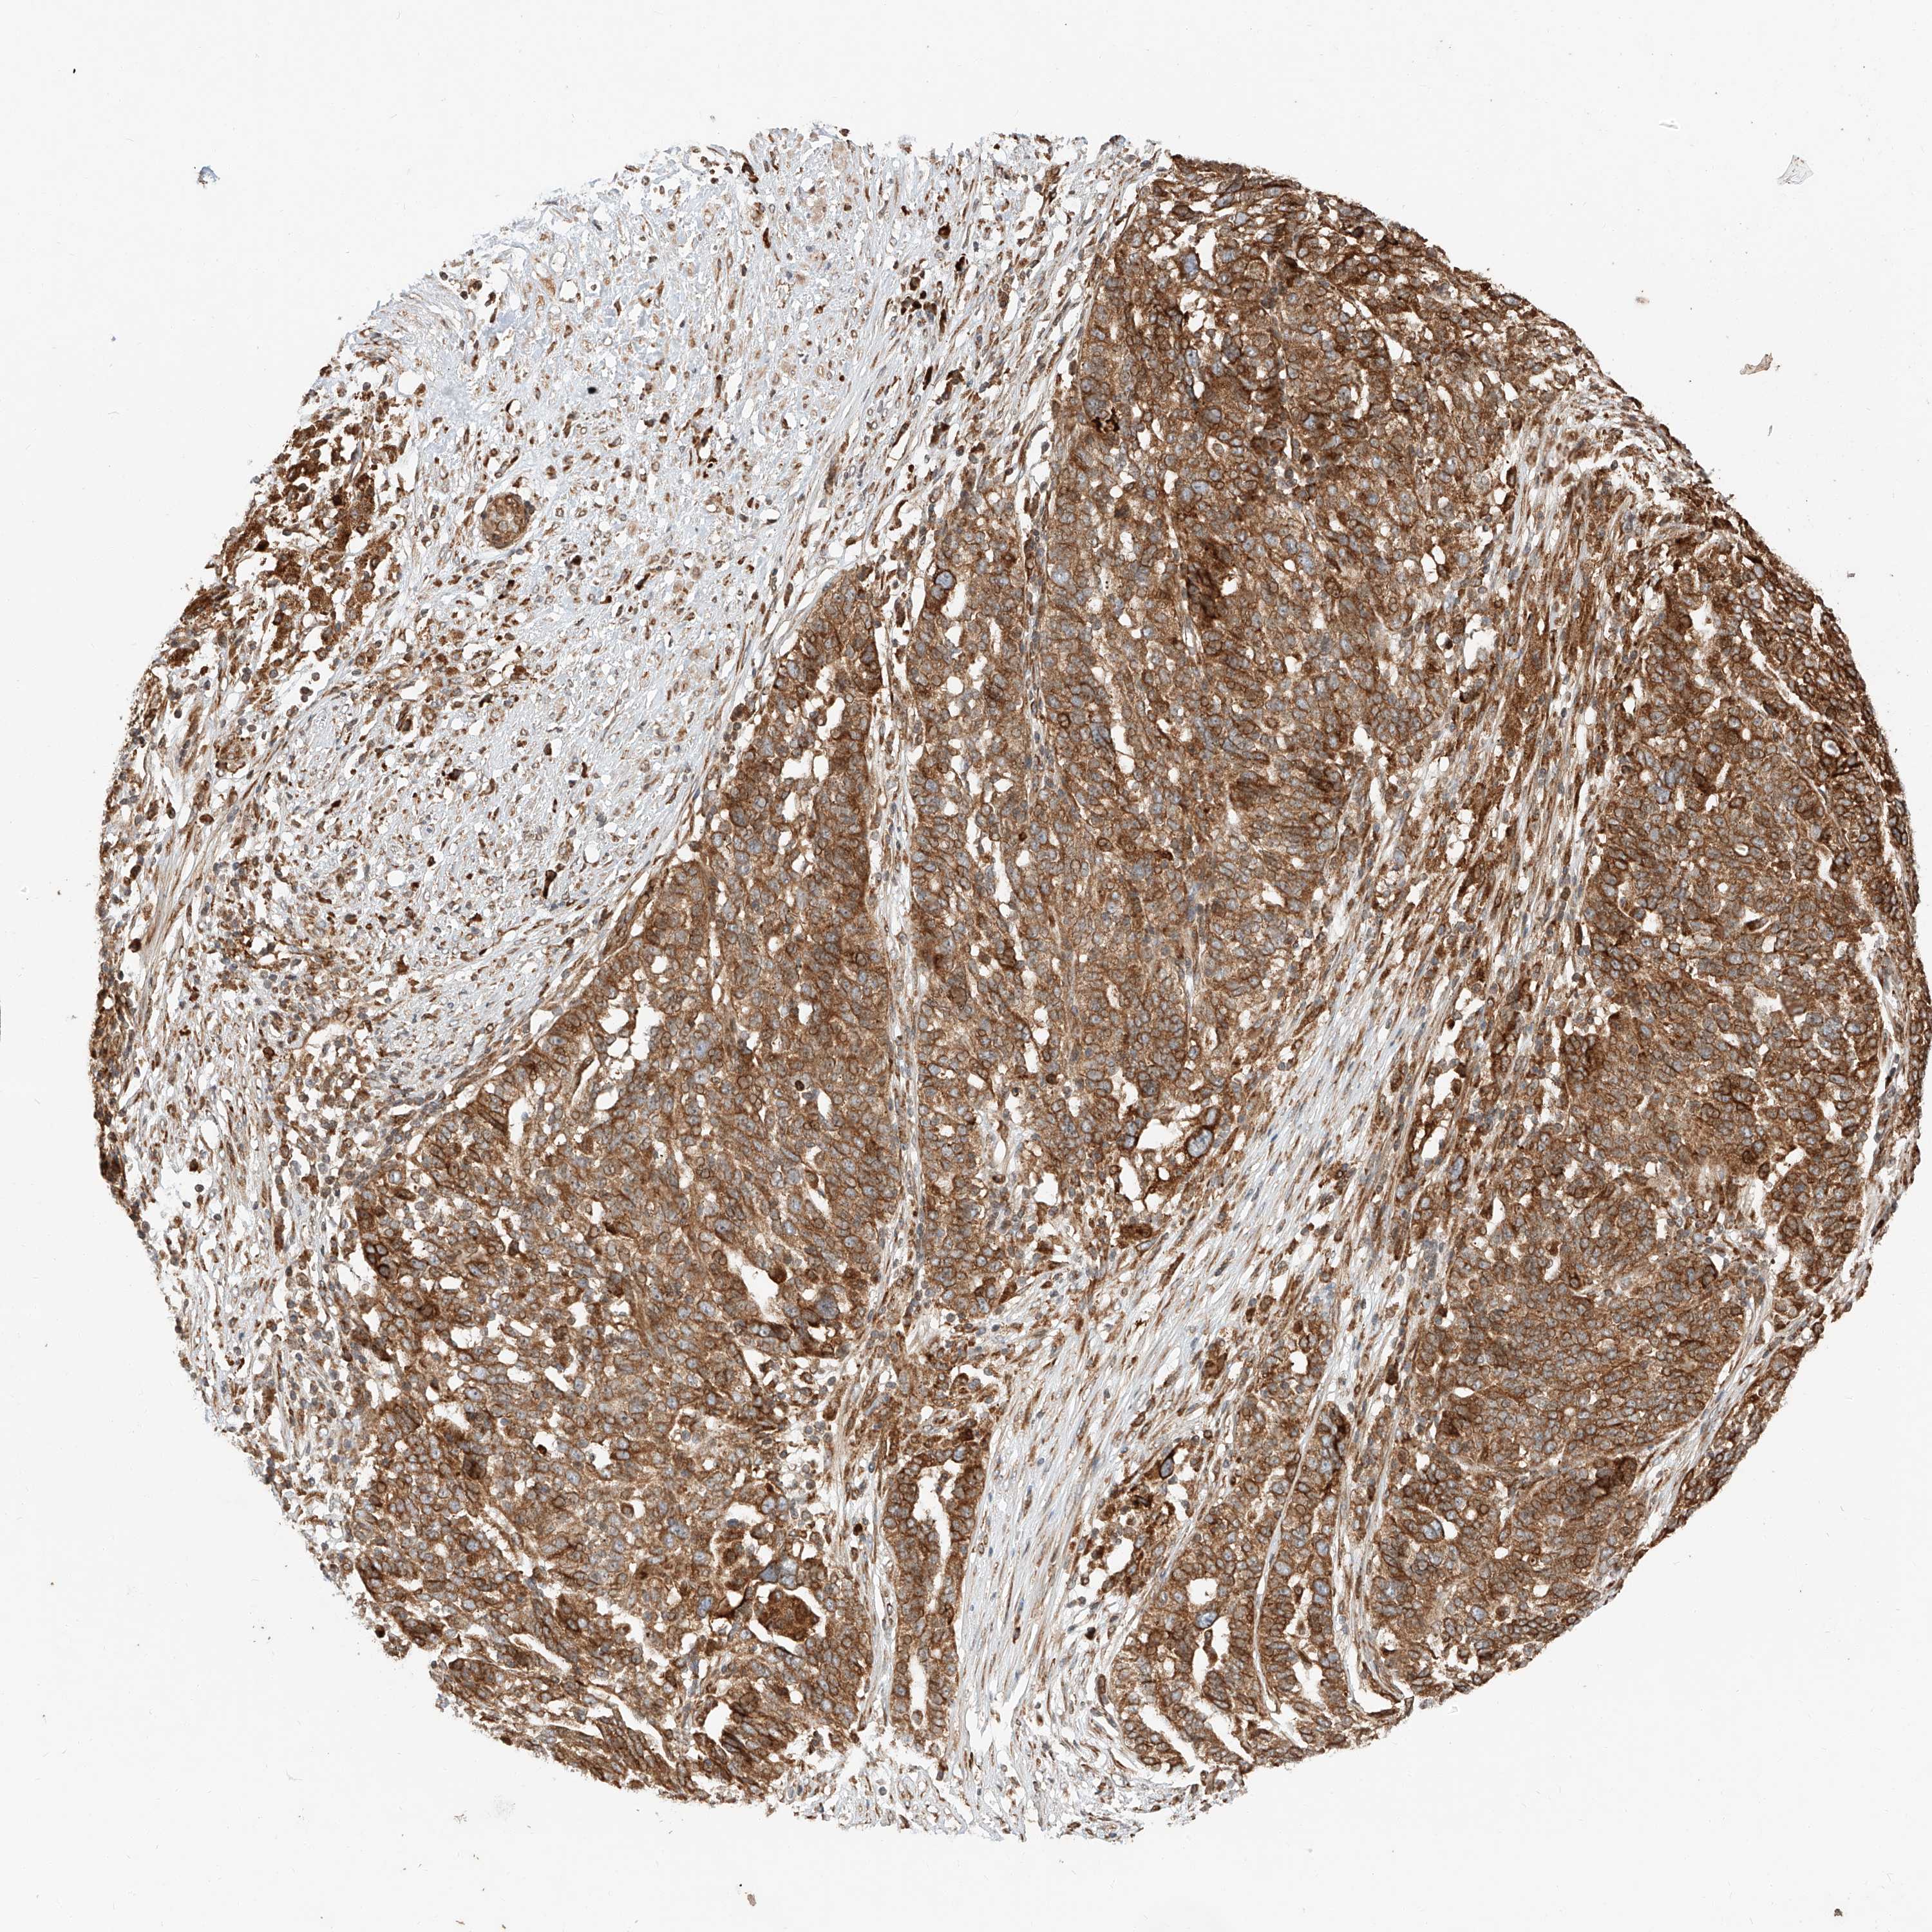

OVARIAN CANCER - Protein expressioni

A mouse-over function shows sample information and annotation data. Click on an image to view it in a full screen mode. Samples can be filtered based on level of antibody staining by selecting one or several of the following categories: high, medium, low and not detected. The assay and annotation is described here.

Note that samples used for immunohistochemistry by the Human Protein Atlas do not correspond to samples in the TCGA dataset.

Antibody stainingi

Antibody staining in the annotated cell types in the current human tissue is reported as not detected, low, medium, or high, based on conventional immunohistochemistry profiling in selected tissues. This score is based on the combination of the staining intensity and fraction of stained cells.

Each image is clickable and will lead to virtual microscopy that enables deeper exploration of all samples and also displays staining intensity scores, fraction scores and subcellular localization as well as patient and tissue information for each sample.

Antibody HPA028860

Staining

High

Medium

Low

Not detected

Intensity

Strong

Moderate

Weak

Negative

Quantity

>75%

75%-25%

<25%

None

Location

Nuclear

Cytoplasmic/membranous

Cytoplasmic/membranous,nuclear

Cystadenocarcinoma, serous, NOS

Carcinoma, endometroid

Cystadenocarcinoma, mucinous, NOS

Carcinoma, NOS